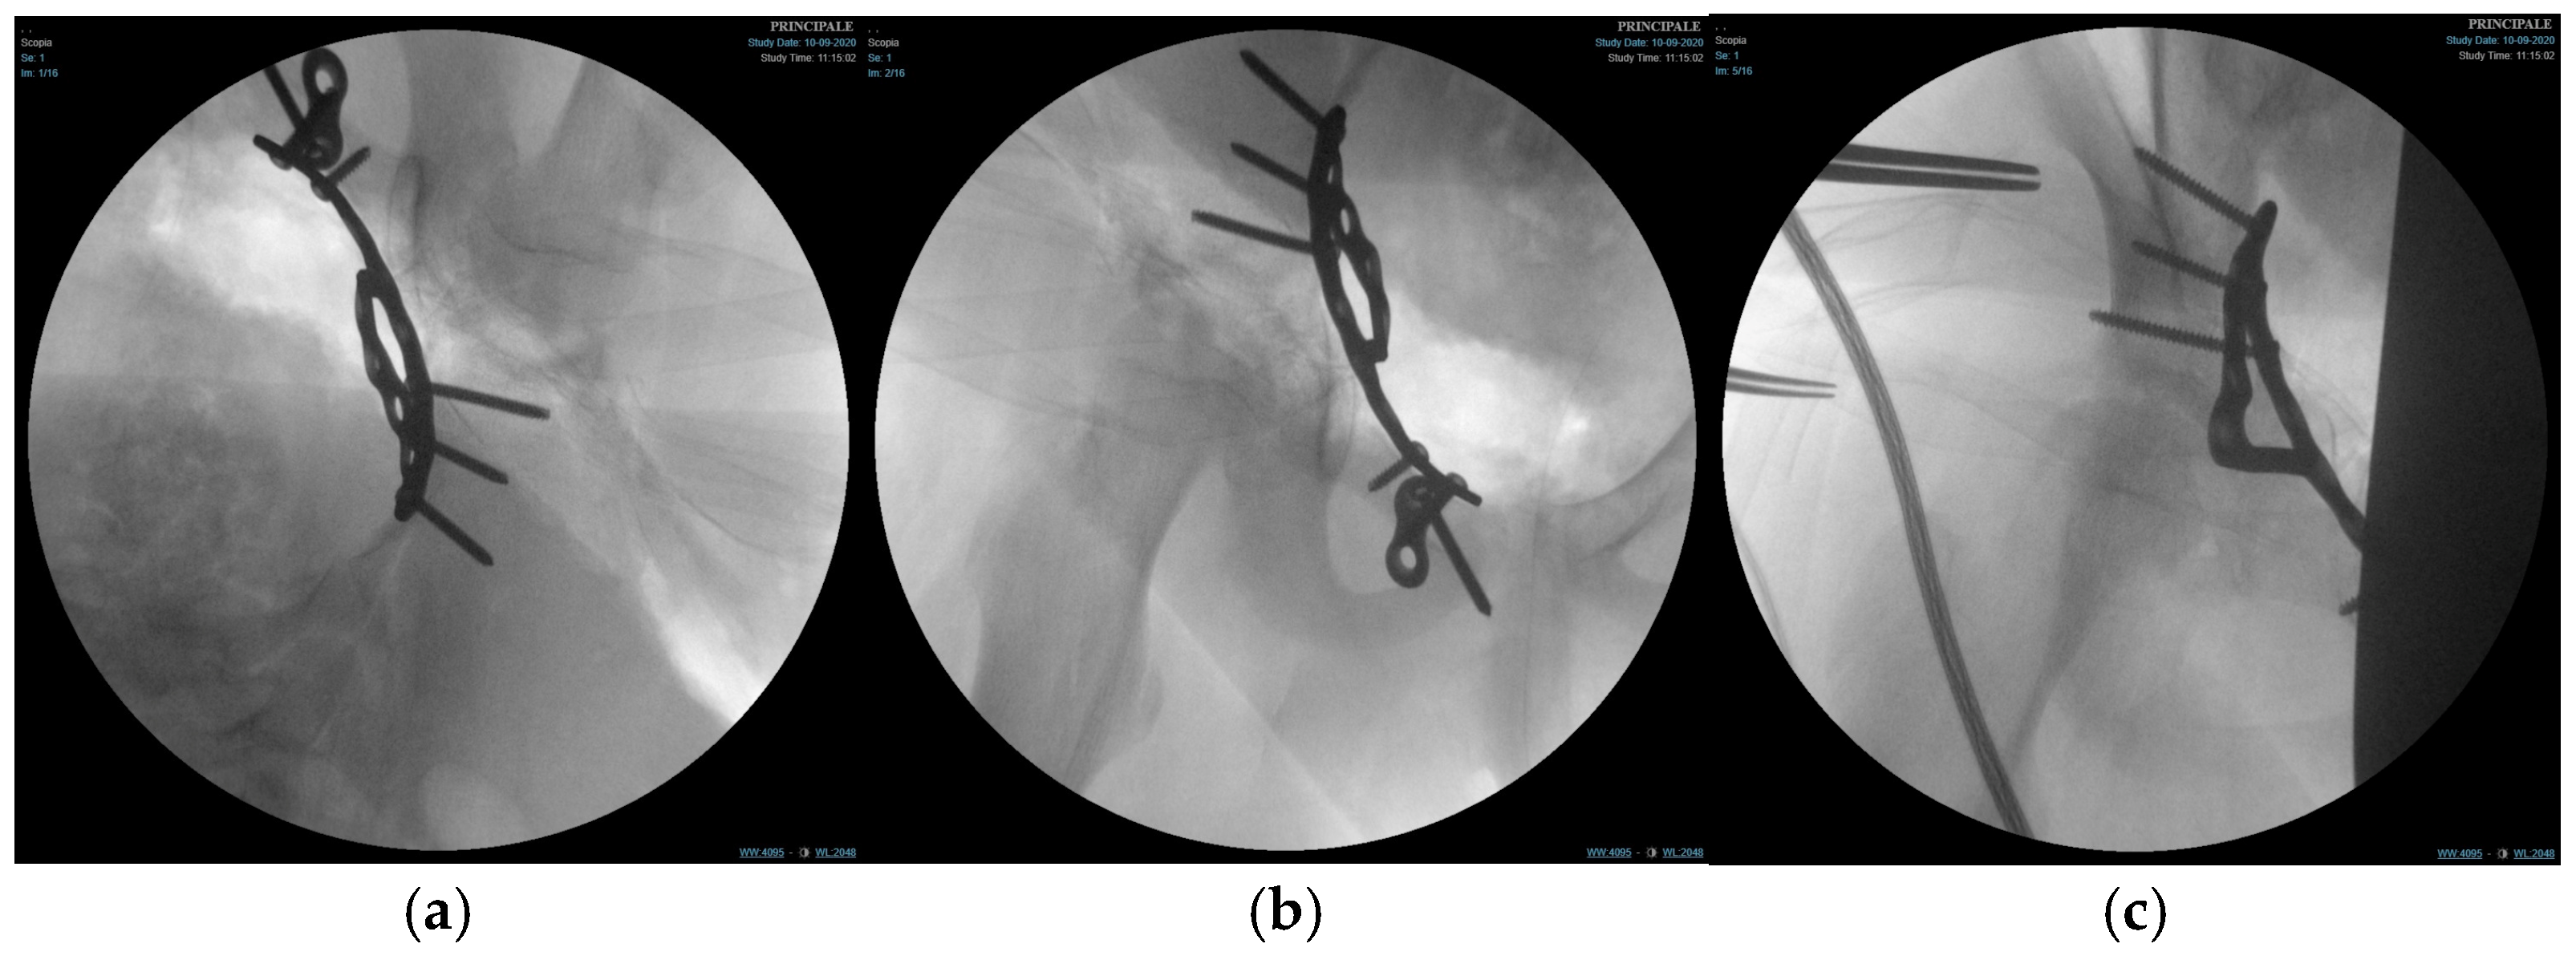

Figure 4.

Fluoroscopic images of the surgical treatment of fracture of right acetabulum. (a) Iliac projection; (b) obturator view; (c) anteroposterior view.

Subperiosteal dissection along the inner pelvis exposed the pelvic brim, anterior column, and quadrilateral surface. The transverse acetabular fracture and separation of the triradiate cartilage were visualised. Fracture reduction was achieved using a combination of pointed reduction clamps, ball-spiked pushers, and provisional K-wires (PRO Pelvis and Acetabulum System, Stryker, GmbH, Bohnackerweg 1 2545 Selzach, Switzerland) under fluoroscopic guidance (anteroposterior, iliac, and obturator oblique views) to restore the contour of the quadrilateral surface and ensure congruent reduction in the femoral head within the acetabulum.

Once an anatomical reduction was obtained, a 3D pre-contoured infrapectineal plate (PRO Pelvis and Acetabulum System, Stryker, GmbH, Bohnackerweg 1 2545 Selzach, Switzerland) was applied along the pelvic brim and quadrilateral surface to provide buttress support. The plate was fixed with multiple cortical screws placed in the supra-acetabular corridor and pubic ramus, avoiding penetration of the joint and the triradiate cartilage. The stability of fixation and joint congruency were confirmed fluoroscopically. (Figure 4) Wounds were irrigated and closed in layers over a drain.